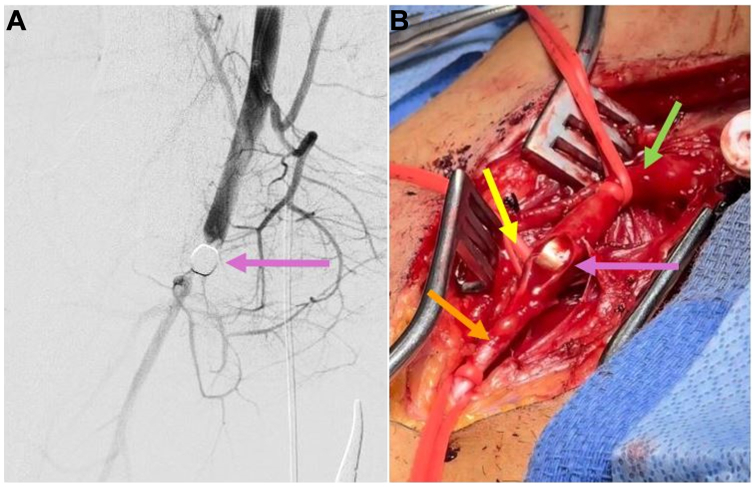

The patient remained hemodynamically stable with ongoing balanced transfusion. He was taken emergently to the hybrid operating room for endovascular repair of his TAI and interrogation of the pulmonary vasculature within 3 hours of initial injury. During ultrasound-guided access, the ballistic fragment made visualization of the right CFA difficult. Thus, right common femoral vein and left CFA access were obtained. The initial aortogram demonstrated extravasation at the mid-thoracic descending aorta (Fig 2, A-C). A Gore TAG 26 mm × 21 mm × 10 mm stent graft (W. L. Gore & Associates, Flagstaff, AZ) was deployed with resolution of aortic extravasation (Fig 2, A-C). The main pulmonary artery (PA) and selective bilateral PA angiograms demonstrated a possible small pseudoaneurysm of a right interlobar PA without extravasation (Fig 2, A-C). Right chest tube output remained minimal after initial insertion; no coiling was performed.

Fig 2.

On aortogram, there was active extravasation appreciated in the mid-thoracic descending aorta (A) that was adequately managed with one Gore TAG stent graft (B). On selective right pulmonary artery (PA) angiography, there was no obvious large pseudoaneurysm or active extravasation requiring intervention at this time (C).

Upon TEVAR completion, the patient did not have palpable distal pulses or Doppler signals in the right lower extremity. An angiogram demonstrated a ballistic fragment within the right CFA (Fig 3, A and B) that had not been palpable on physical examination. A standard right CFA exposure was performed with control of the CFA, superficial femoral artery (SFA), and profunda femoris using Potts ties. The patient was heparinized. A linear arteriotomy was made on the anterior wall of the CFA with removal of the bullet at the bifurcation of the SFA and profunda (Fig 3, A and B). Good forward and backward bleeding were confirmed with no endothelial damage appreciated. A patch angioplasty was performed with bovine pericardium and running 6-0 Prolene sutures. With percutaneous access maintained, suction thrombectomy was performed of the SFA, popliteal, and tibial arteries with completion angiography ensuring no remaining distal clot. The groin incision was closed in layers. A four-compartment right lower extremity fasciotomy was performed given ischemia time of >4 hours. The thoracotomy was closed with bilateral chest tubes in place. The patient was transferred to the intensive care unit.

Fig 3.

Right lower extremity arteriogram demonstrated a bullet fragment within the common femoral artery (CFA) limiting antegrade blood flow (A). Right femoral cutdown was performed with control of the right CFA (green arrow), profunda femoris (yellow arrow), and superficial femoral artery (SFA) (orange arrow) with CFA arteriotomy performed for bullet removal (purple arrow) (B).